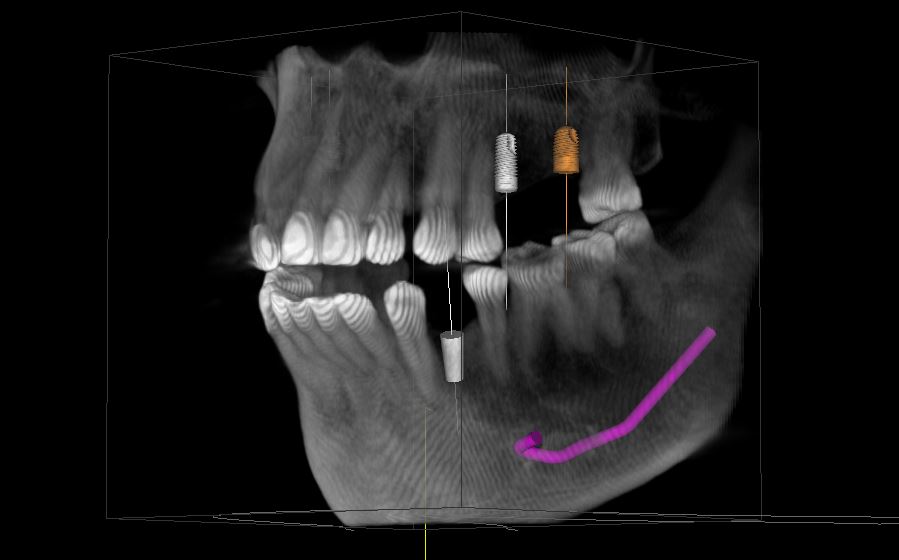

Dental implants are artificial tooth roots that provide a permanent base for fixed, replacement teeth. Compared to dentures, bridges and crowns, dental implants are a popular and effective long-term solution for people who suffer from missing teeth, failing teeth or chronic dental problems.

The ideal candidate for a dental implant is in good general and oral health. Adequate bone in your jaw is needed to support the implant, and the best candidates have healthy gum tissues that are free of periodontal disease.

Dental implants are intimately connected with the gum tissues and underlying bone in the mouth. Since periodontists are the dental experts who specialize in precisely these areas, they are ideal members of your dental implant team. Not only do periodontists have experience working with other dental professionals, they also have the special knowledge, training and facilities that you need to have teeth that look and feel just like your own. Your dentist and periodontist will work together to make your dreams come true.